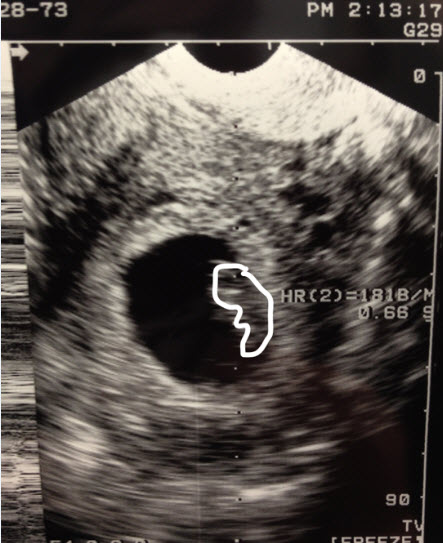

It still feels a virtual sometimes. I know I’m sleepy and hungry and my boobs are sore and I saw the heartbeat last Wednesday and by all definitions I am pregnant. Yet, hanging around moms-to-be with big bellies and moms with babies makes it oddly less real rather than more–there’s nothing to look at yet. It’s more of an idea. It’s something I tell rather than show.